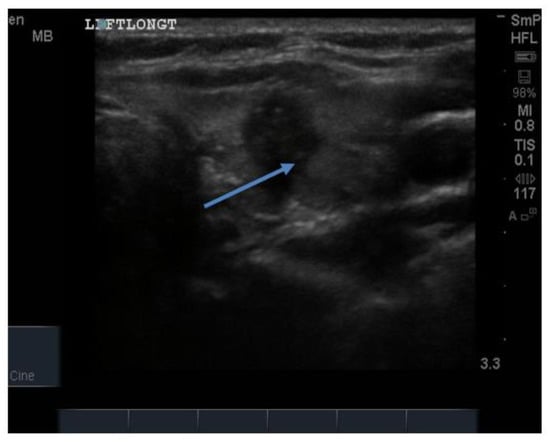

14. Parathyroid Disease

Because the senior author (JW) routinely measures serum calcium, parathyroid hormone (PTH) and vitamin D in his patients, hyperparathyroidism due to a benign adenoma of one of the parathyroid glands appears to be much more common than previously thought. The parathyroid glands are hidden behind the thyroid and so may be obscured by thyroid nodules, although they can often be seen in the longitudinal view below the lobes, as a hypoechoic lesion of around 1 cm in diameter (Figure 18).

Figure 18.

Thyroid ultrasound from a patient with hyperparathyroidism showing a hypoechoic lesion below the right thyroid lobe that was confirmed to be a parathyroid adenoma at surgery.

The parathyroid adenoma is typically hypoechoic by comparison to the nearby thyroid tissue, which is consistent with the author’s experience. However, only about 50% of subsequently proven parathyroid adenomas are seen on ultrasound and even the Sestamibi nuclear scan fails to pick them up in about 30% of cases.